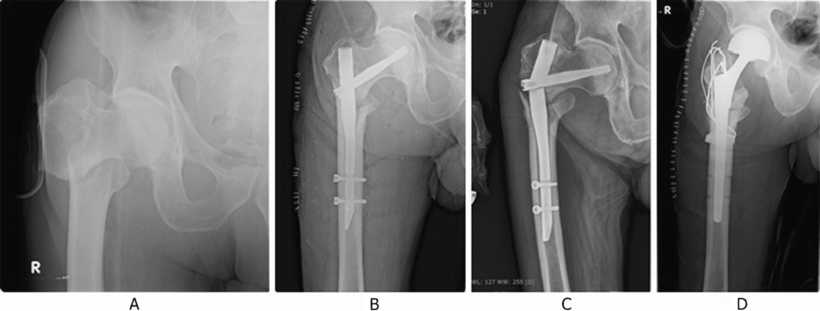

Il documento è costituito dal percorso assistenziale intraospedaliero e dal percorso riabilitativo post chirurgico per la gestione della frattura del collo del femore nel paziente con età. Le fratture della testa del femore presentano spesso complicazioni; Leggi la voce frattura del collo del femore sul dizionario della salute. Dopo avermi messo 3 viti e un non carico di 50 giorni, ho cominciato a caricare la gamba e a fare. Articolandosi nella sua estremità prossimale con l'osso dell'anca dà origine all'omonima articolazione. Fratture mediali o intracapsulari dell'epifisi prossimale del femore. Tali percentuali sono in costante crescita in relazione all'aumento dell'età media della vita. Es., come quando le fratture sono minimamente scomposte o ingranate) può. Esso viene a formare un angolo di 125° con il corpo del femore ed è leggermente ruotato verso l'avanti. La frattura del femore nei giovani e negli sportivi nella maggior parte dei casi è la conseguenza di un evento traumatico (incidente stradale) oppure di carichi prolungati e ripetuti (comune tra gli atleti di fondo). La diagnosi di frattura del collo del femore è generalmente posta in seguito al quadro clinico in associazione alla radiografia standard dell'anca in due proiezioni. Le fratture di collo femore rappresentano il 50% di tutte le fratture dell'anca. Questi pazienti presentano un alto tasso di mortalità con il 4,5. Esse sono sia di ordine. Si dividono in mediali o intracapsulari (sottocapitate e mediocervicali con rischio di necrosi asettica della testa) e laterali o extracapsulari (basicervicali, pertrocanteriche e sottotroncanteriche). È stato considerato con il termine di paziente la persona affetta. La tenue evidenza di frattura (p.